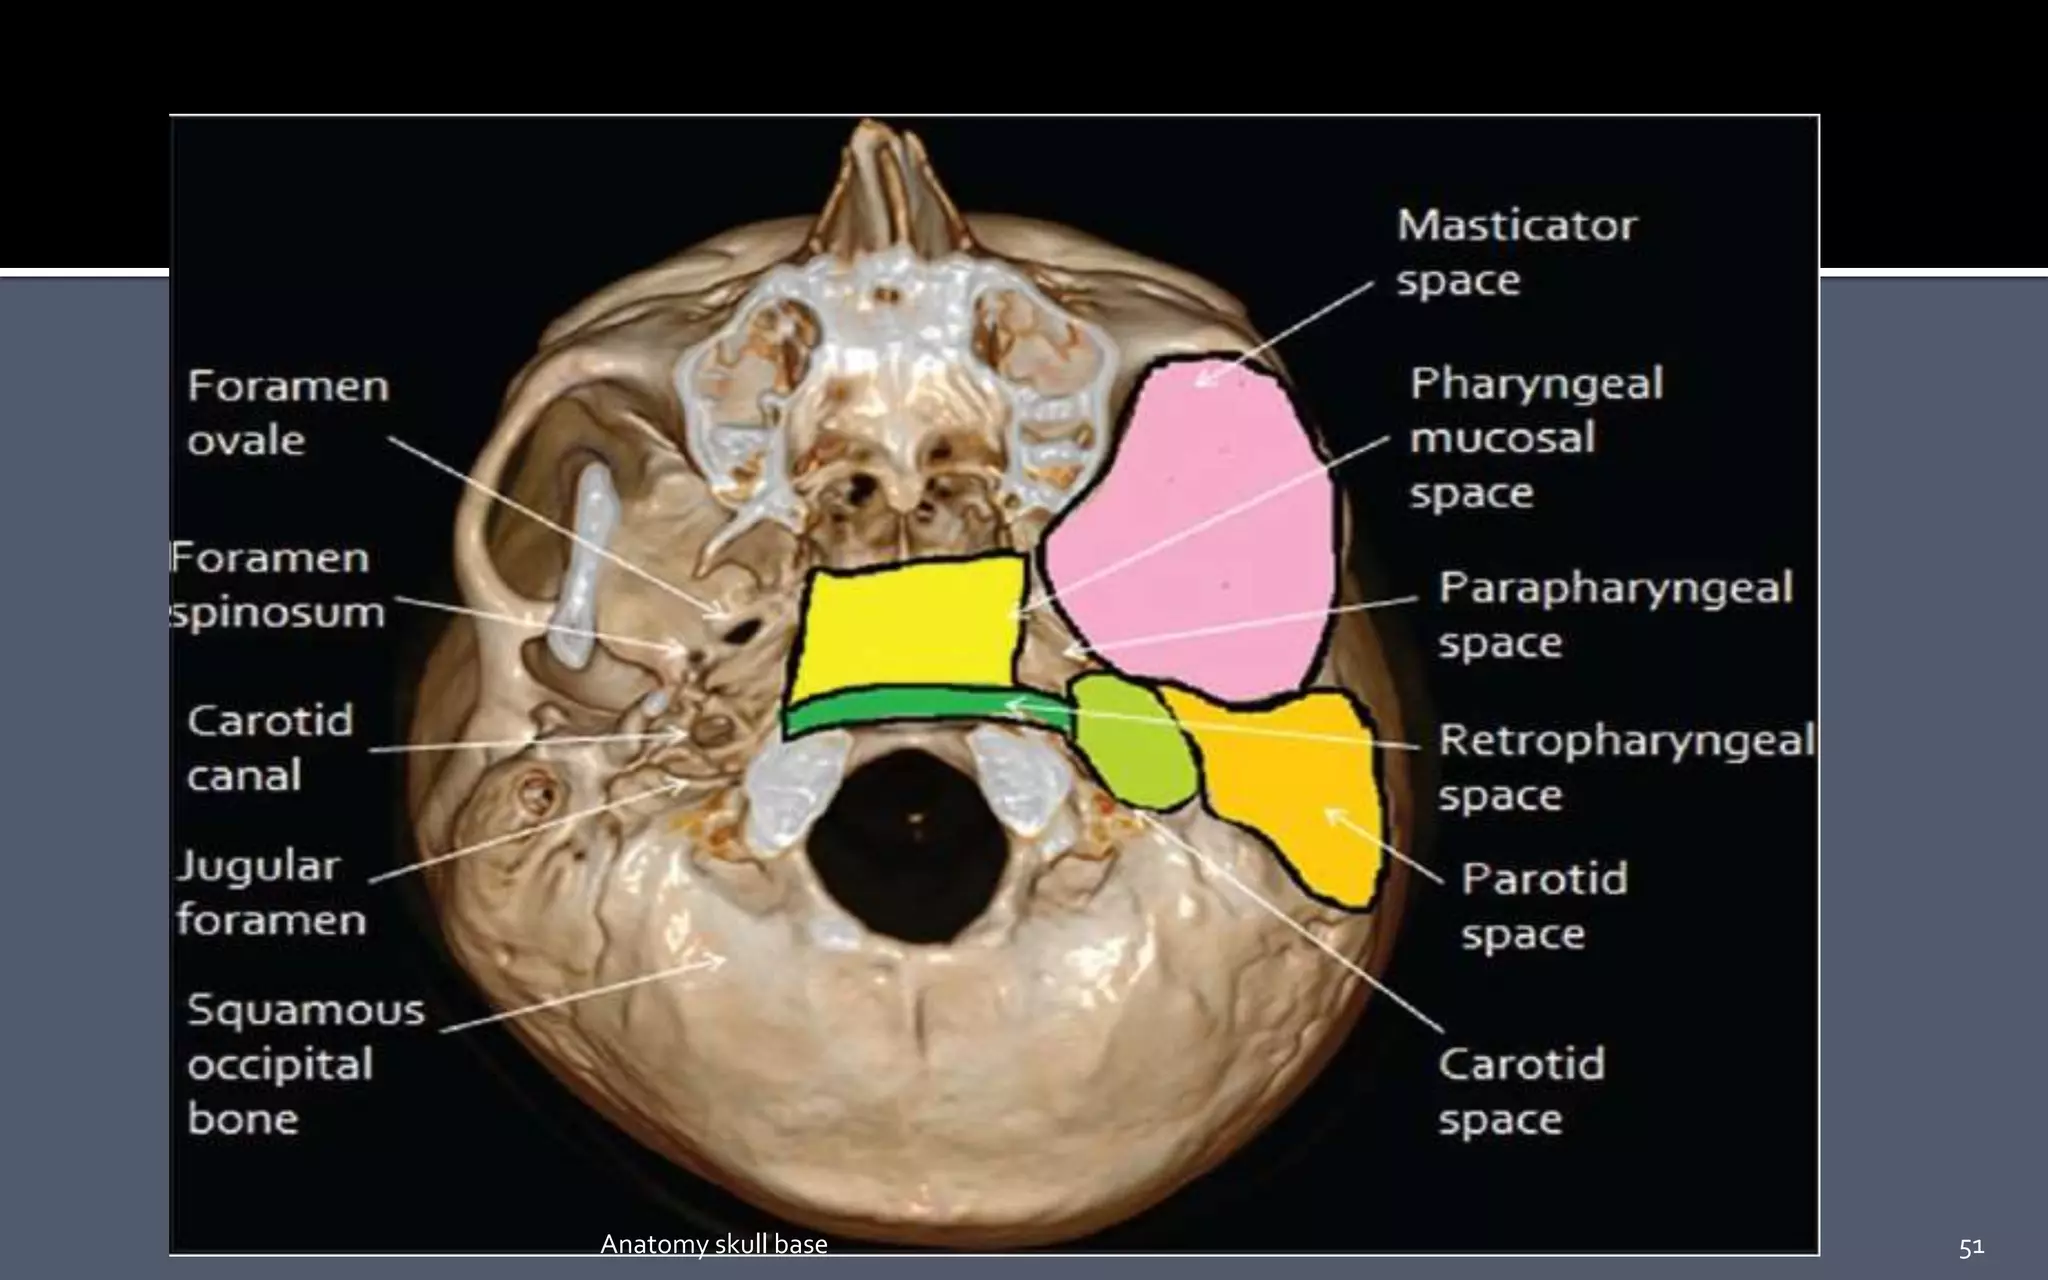

 Parapharyngeal , masticator, carotid, and retropharyngeal spaces are

seen in close contact with the skull base along their cephalad aspect .

 Masticator space connects the mandible to the skull base. Odontogenic

infections and oropharyngeal squamous cell carcinoma can tract along

masticator space to the base skull.

Intracranial extension of the tumor can occur

via third division of trigeminal nerve, mandibular nerve (perineural

spread) through the foramen ovale.

 Vascular lesions such as jugular vein thrombosis and neural tumors such

as Schwannoma, Neurofibromas, and Paraganglioma are seen in the

carotid space.

51Anatomy skull base